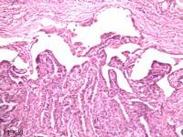

• 甲狀腺微小癌

628健康網為您分享有關甲狀腺微小癌的癥狀,甲狀腺微小癌的治療方法,甲狀腺微小癌的預防知識,甲狀腺微小癌的癥狀圖片,甲...